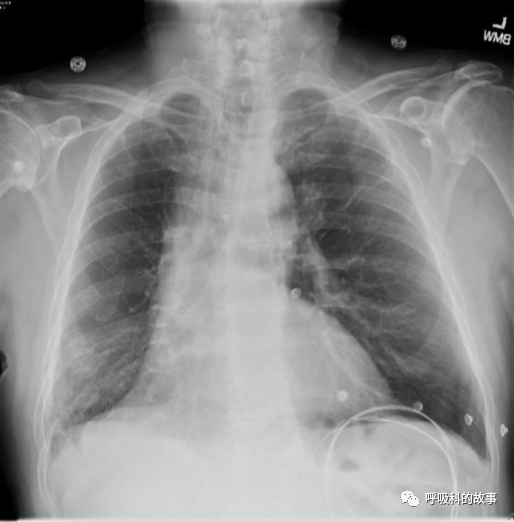

最早的胸片顯示右肺容積變小,伴有有網狀陰影(圖1)。